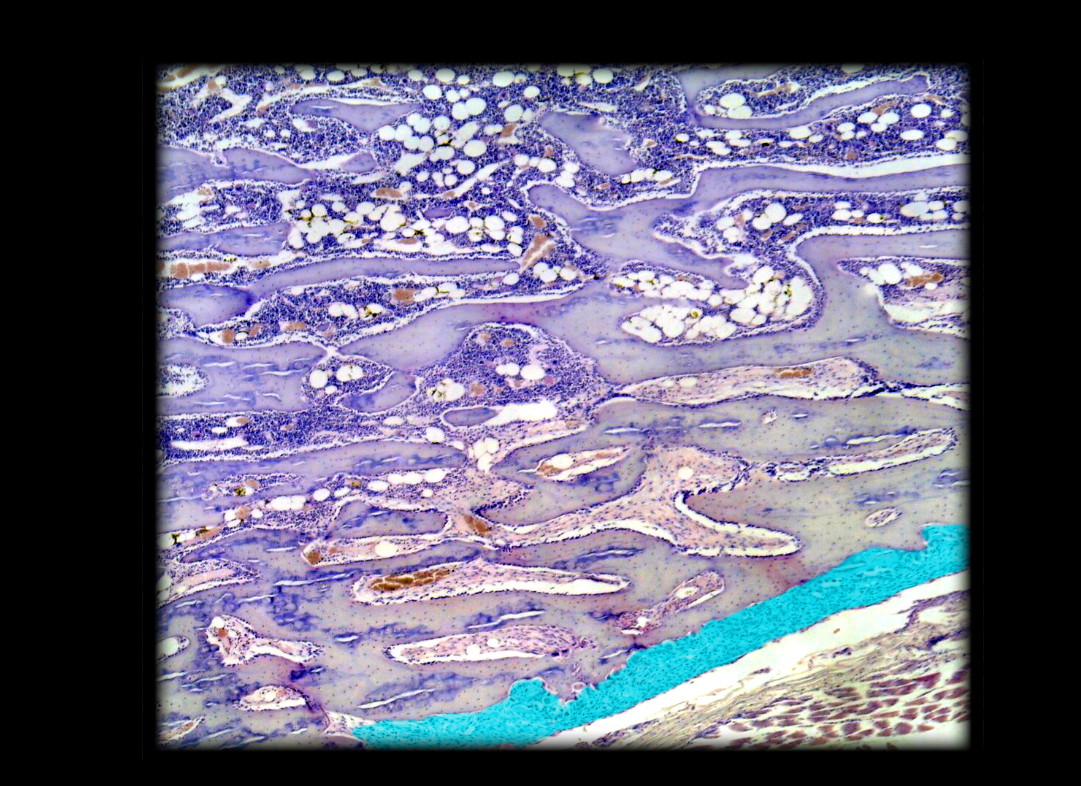

Marrow cavity in spongy bone

17

New cards

Trabecula of spongy bone